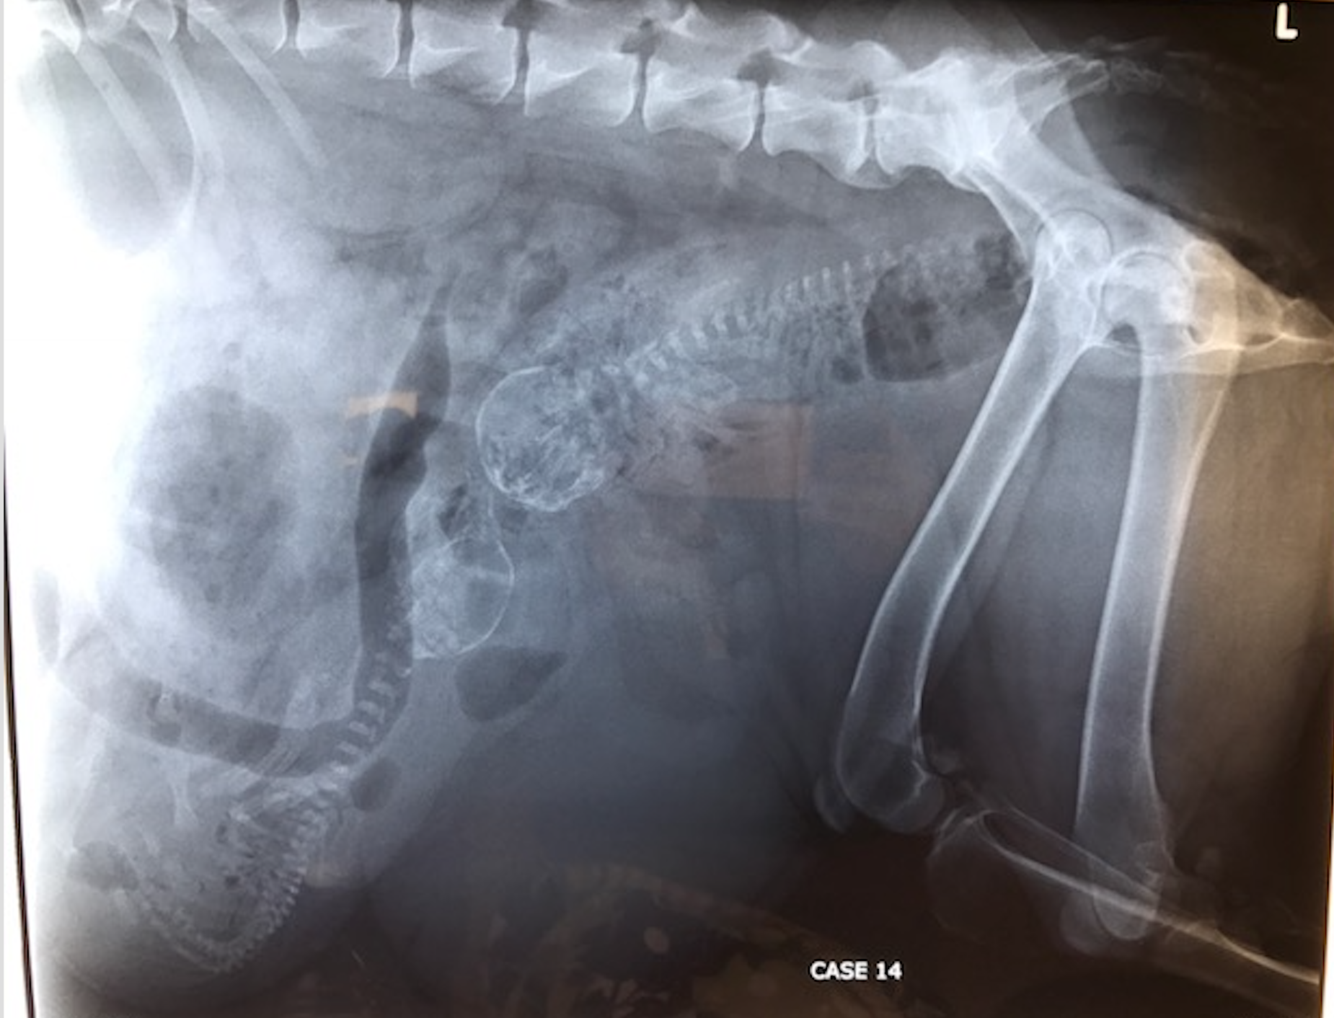

Pip

1 yo MN Ragdoll

Trodden by a horse

HR 138 RR 32 MM pale, lethargic, distended painful abdomen

DDX for decreased intraserosal detail?

What is most likely?

What structures can you see?

Are there any MSK abn?

What procedure has been performed? Describe how you would perform this study.

Can you namet he phases of the excretory urogram?

Is there a rupture of the urinary tract? What is the most likely cause of Pips loss of serosal detail?

Excretory urogram is used to visualize the kidneys and ureters while the other contrast studies are used to visualise the lower urinary tract.

AKA IV Pyelogram. An iodinated contrast agent such as iohexol is injected IV. Contrast agent is rapidly concentrated and excreted by the kidneys.

Nephrogram phase- the renal cortex and medulla opacity– rate of renal opacification and wash out of the contrast agent provides a rough indication of the filtraion ability of the kidneys.

The contrast agent is excreted by the nephrons and accumulates within the renal pelvis- the pyelogram phase. The size and shape of the renal

pelvis can be assessed

Cystogram- Almost immediately, the contrast agent will pass down the ureters, and into the

urinary bladder, producing a ‘cystogram’.